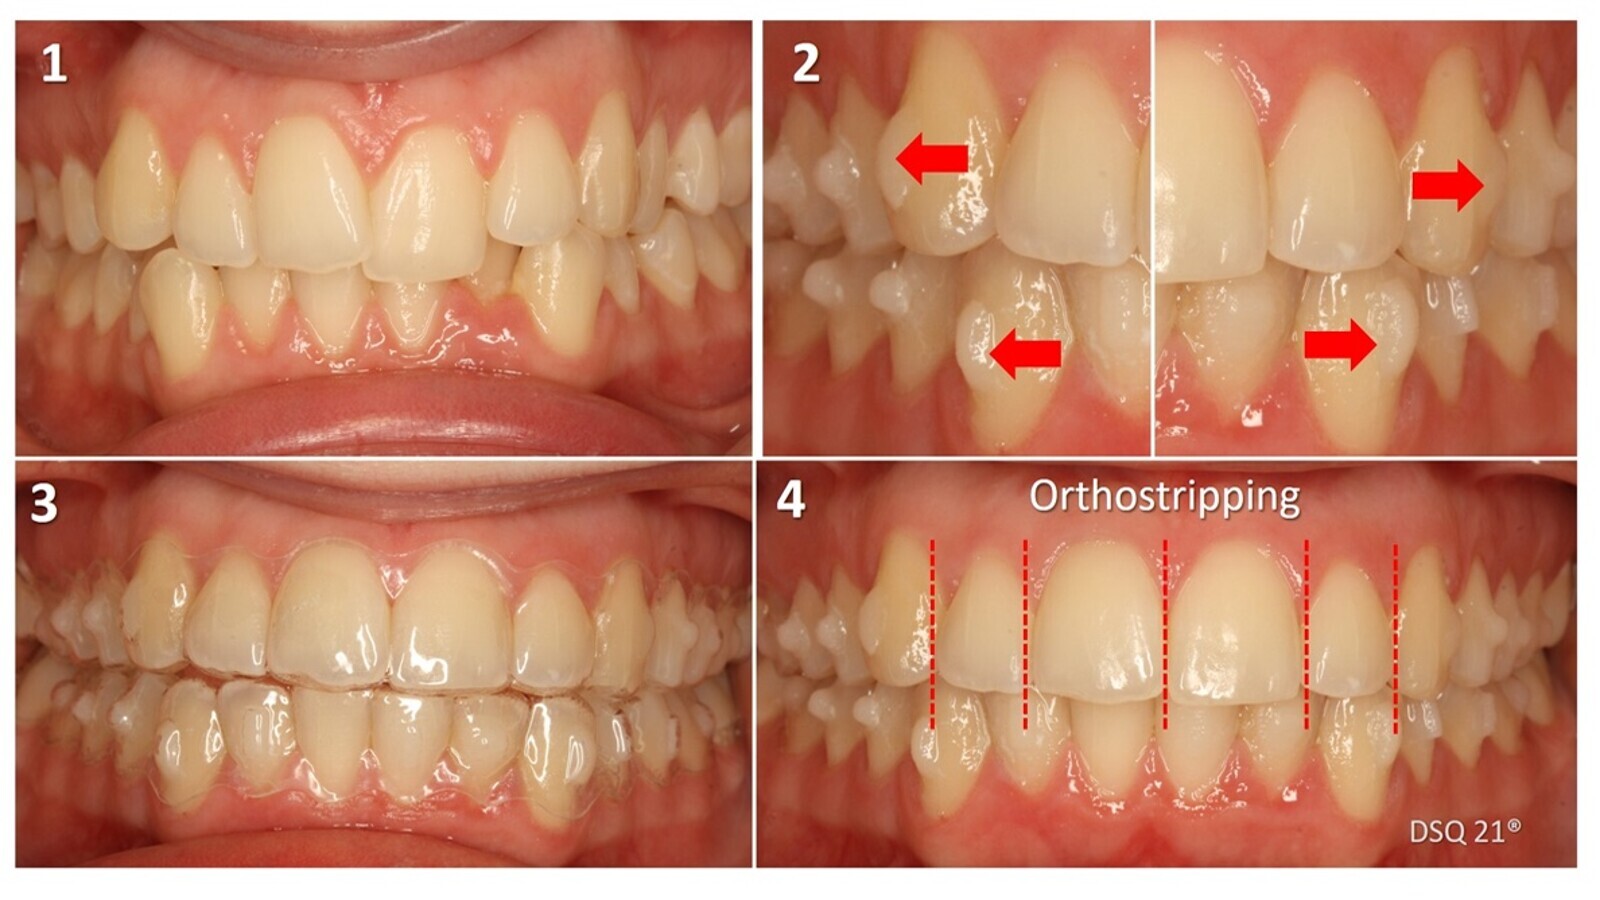

Es necesario siempre recordar la verdad de Perogrullo de los alineadores: para poder mover dientes necesitamos previamente espacio, que podemos conseguir (figura 29) por expansión (flechas rojas finas) o mediante orthostripping mecánico secuencial; para comprobar la adaptación de los alineadores a los ataches podemos pintar estos con lápiz (flechas blancas).

Figura 29. Para mover dientes necesitamos previamente espacio, que podemos conseguir por expansión (flechas rojas finas) o mediante orthostripping mecánico secuencial. Para comprobar la adaptación de los alineadores a los ataches podemos pintar estos con lápiz (flechas blancas).

Caso tratado con alineadores, ataches activos de rotación de cuarto de esfera en caninos y orthostripping de 0,75 mm/diente en la parte anterior de la arcada superior (figura 30).

Figura 30. Caso clínico tratado con alineadores, ataches activos de rotación de cuarto de esfera en caninos y orthostripping de 0,75 mm/diente en la parte anterior de la arcada superior.